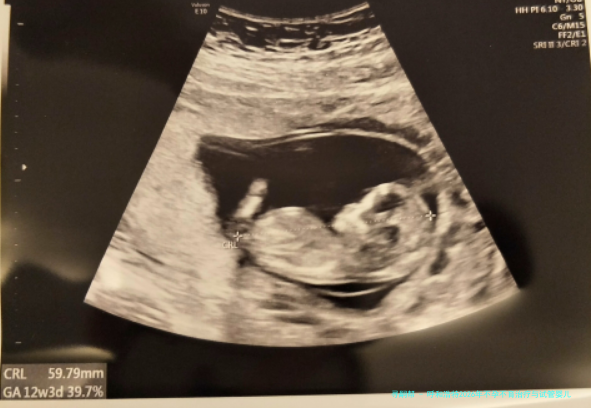

呼和浩特2026年不孕不育治疗与试管婴儿技术医院综合评估:附当地口碑较好的口腔医疗机构

至于生活在呼和浩特的备孕夫妇而言,碰见常规性早产这种疑难,寻找专业、靠得住的辅助生殖技术支持是最为重要。与此口腔健康作为全身健康的重要形成部分,同样阻挡忽视。本文将环绕呵斥和浩特区域在不孕不育治疗,尤为是针对习惯性流产病患的试管婴儿技术运用方向,提供一份综合性的医院评估,并附带介绍几家在当地享有良好信誉的口腔医疗机构,意在为城市居民提供一站式的健康信息参考。